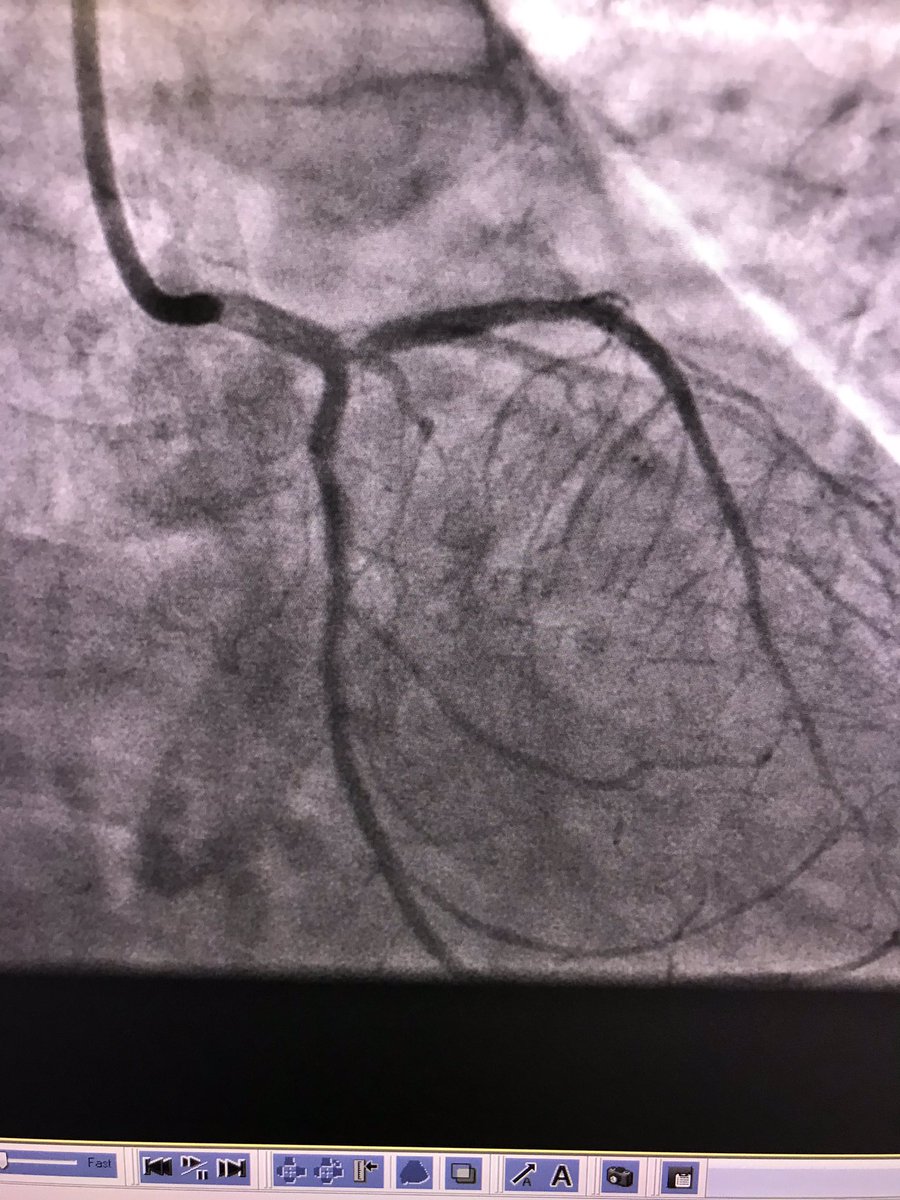

#safefemoral #protectedpci 62 m anterior stemi ivus guided into left main . Ef 50% at d/c

istentem's tweet image. #safefemoral #protectedpci 62 m anterior stemi ivus guided into left main . Ef 50% at d/c